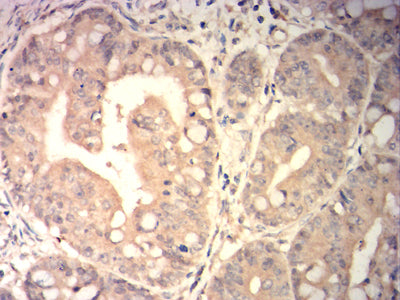

分类: 科研抗体货号: 31896别名: CT22; SPA17; SP17-1应用: IHC,FCM反应种属: Human